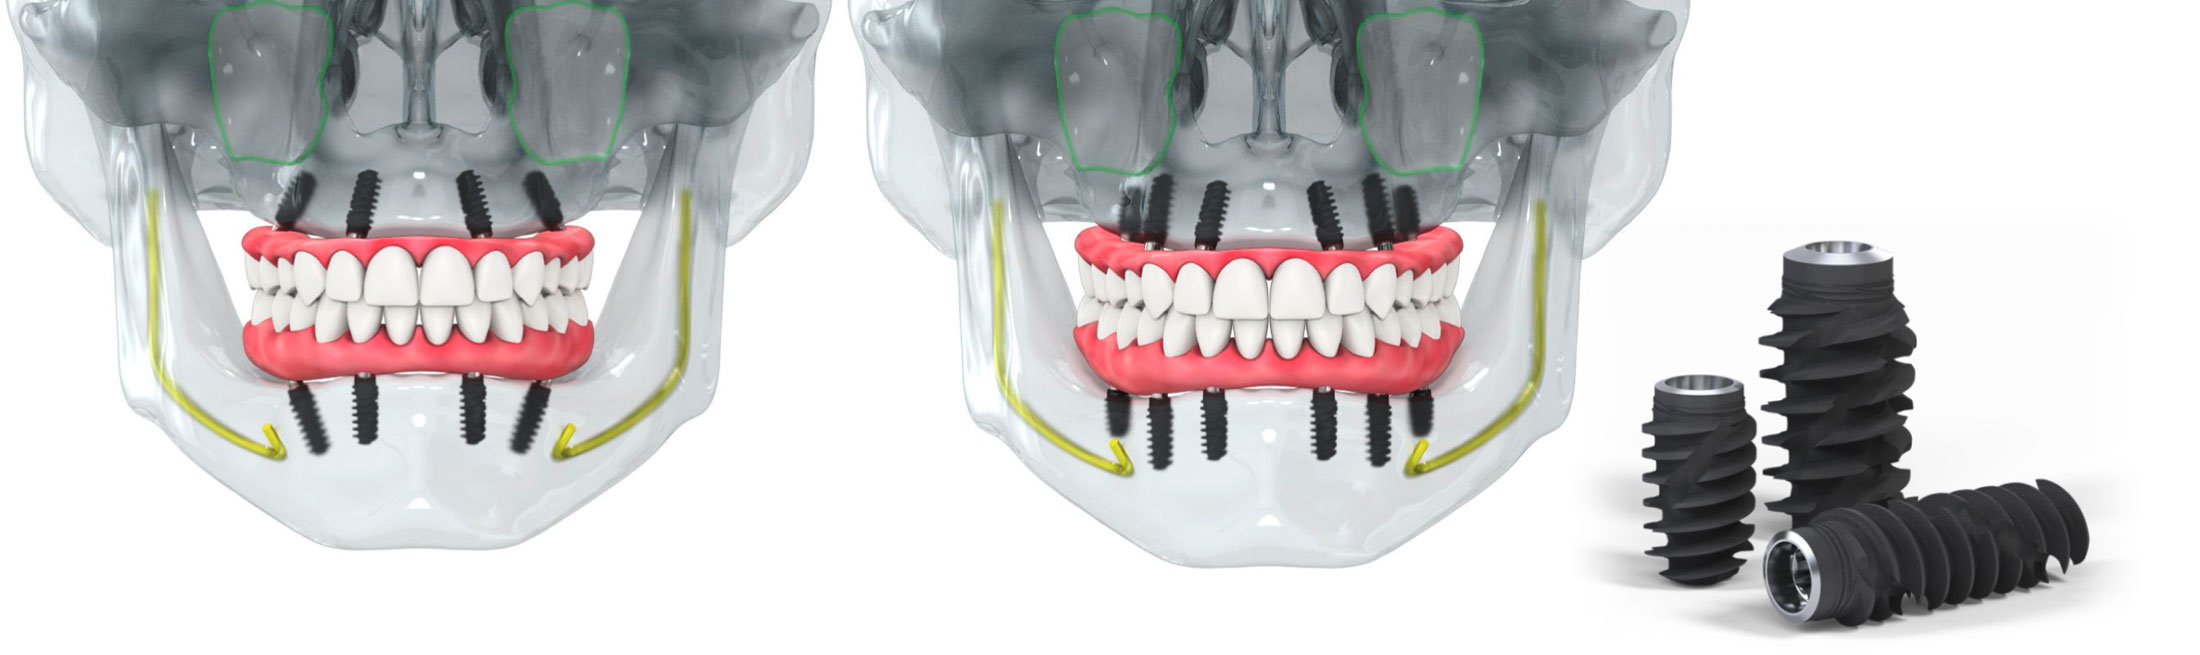

All-on-4 và All-on-6 là phương pháp cấy ghép Implant toàn hàm bằng cách sử dụng 4 hoặc 6 trụ Implant để nâng đỡ một hàm răng cố định.

- Giảm số lượng trụ Implant nhưng vẫn đảm bảo chịu lực và độ ổn định cao

- Có thể hạn chế hoặc tránh ghép xương nhờ kỹ thuật đặt trụ nghiêng thông minh

👉 Bác sĩ sẽ chỉ định All-on-4 hay All-on-6 dựa trên tình trạng xương hàm, lực nhai và nhu cầu của từng khách hàng.

- Trụ Implant tích hợp chắc chắn vào xương hàm

- Ngăn ngừa tiêu xương

- Duy trì cấu trúc khuôn mặt